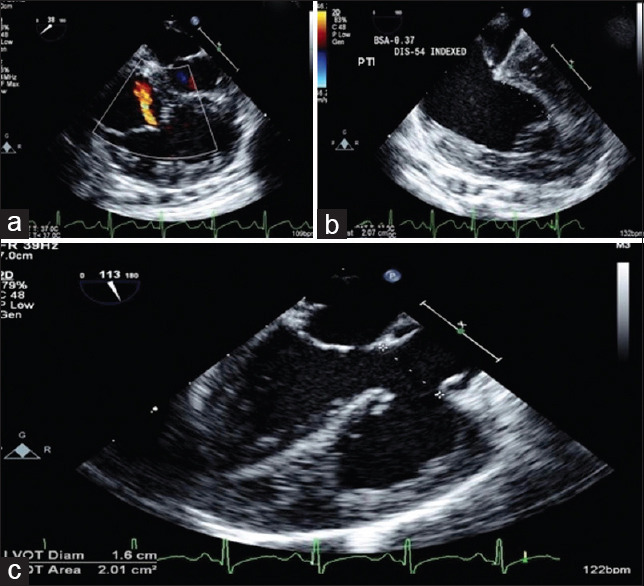

Association of Ebstein's anomaly of tricuspid valve (TV) with tetralogy of Fallot (TOF) is extremely rare. Their coexistence is unique as they modify each other's physiology. We report a case of a girl child having this rare combination along with Diamond-Blackfan syndrome awaiting a bone marrow transplant. She underwent intracardiac repair for TOF along with cone reconstruction of the TV, as tricuspid regurgitation of Ebstein's anomaly would worsen with TOF correction alone. Through this surgery, we aimed to achieve a competent pulmonary valve using a transannular patch with a monocusp and adequate relief of the right ventricular tract obstruction, thus preserving the right ventricular function, as both can affect the repaired TV function in the long term. The child had an uneventful postoperative course and is asymptomatic on follow-up.